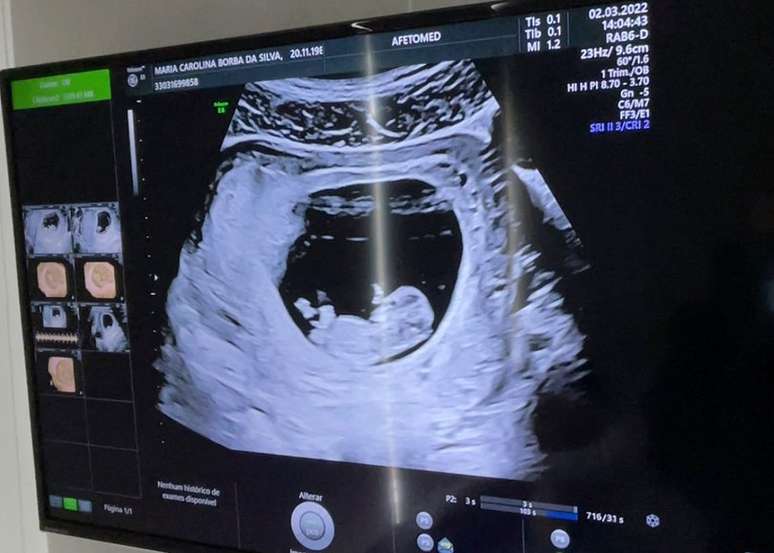

“Oi, titias, já tenho bracinhos e perninhas”: Carol Borba compartilhou imagem do ultrassom (Reprodução/ Instagram)